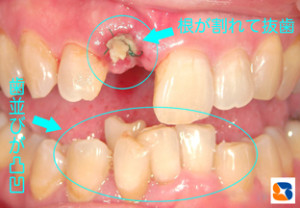

トラブル 根が割れる

コラム「トラブル 根が割れる」の画像